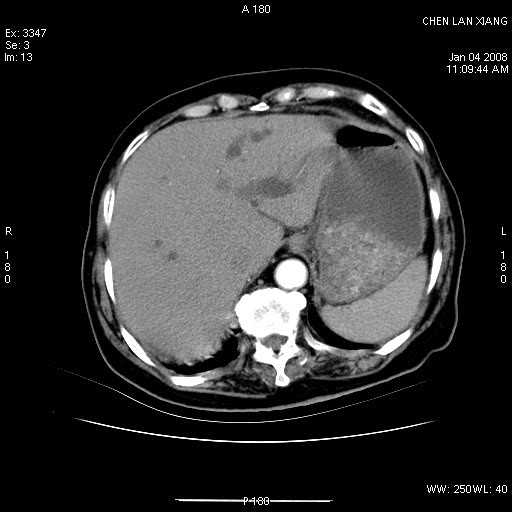

标题: CT11180:女,76岁,腹痛3-4天 [打印本页]

标题: CT11180:女,76岁,腹痛3-4天

女,76岁,腹痛3-4天,b超示:肝内实性肿物,胆囊强回声,胆总管扩张.

考虑:1、胆总管下端结石伴梗阻性肝内外胆管扩张(肝左叶外侧段肝内胆管多发结石、胆管炎);

2、肿囊癌累及肝,不除外 黄色肉芽肿性胆囊炎。

1 胆总管末端结石伴肝内胆管结石,肝内外胆管扩张。2 胆囊扩大,胆囊壁不规则增厚,内见软组织密度影。考虑:慢性胆囊炎,不除外胆囊癌!

标题: 肝右叶病灶

胆囊癌侵犯肝右叶?

1)胆囊癌伴肝脏转移。2)胆总管下端结石、肝内胆管结石伴肝内外胆管扩张。